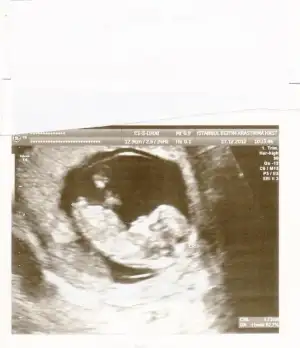

dr soylemeden siz gorun genital nub teorisi ( bebegin cinsiyeti)

kızlar ben bu seferki ultrason resimlerimden bebeğimi seçemiyorum ibirisnden biraz belli gibi kafası falan ama yanlışmı diyorum siz seçebiliyomusunuz bu resimlerde kuzum nerde:26::26::26:

Gordugum nubsa erkek

Bas kaldirmis nub paralellik yok :)))

kızlar bu da benimkinin son resmi :)) doktor erkek olabilir belki dedi orası çok karışık ama net bişey söyleyemem dedi bide siz bakın bakalım benim de içime hep kız doğuyordu çini rusu musu hepsinde de kız çıkıyordu bilemedim bende şimdi :))

hakikaten cok karisik cnm yaaa kac haflaik resim buuu

14 haftalık canım ya valla bende bişey anlamadım bu işten bir öncekinde kız gibi duruyordu doktor erkek olabilir deyince şaşırdım bende ama kesin değil dedi oda senin gibi çok karışık orası diyorr :))hakikaten cok karisik cnm yaaa kac haflaik resim buuu

14 haftalık canım ya valla bende bişey anlamadım bu işten bir öncekinde kız gibi duruyordu doktor erkek olabilir deyince şaşırdım bende ama kesin değil dedi oda senin gibi çok karışık orası diyorr :))

bence hic karisik degil ve net kiz:))

aslinda resmin tahmin icin uygun degil popsu asagida olmali tahmin icin ama bana cok parallel geldi, eger 13 haftada gittiysen bu nub kiz nubu:) ama onceden gittiysen aci degisebilir sonradan.

pardon alinti yapinca resmini daha net gordum aksine yukari dogru aci var sanki ama iste pozisyonu yanlis, pozisyona gore nubun gorunusu degisiyor.